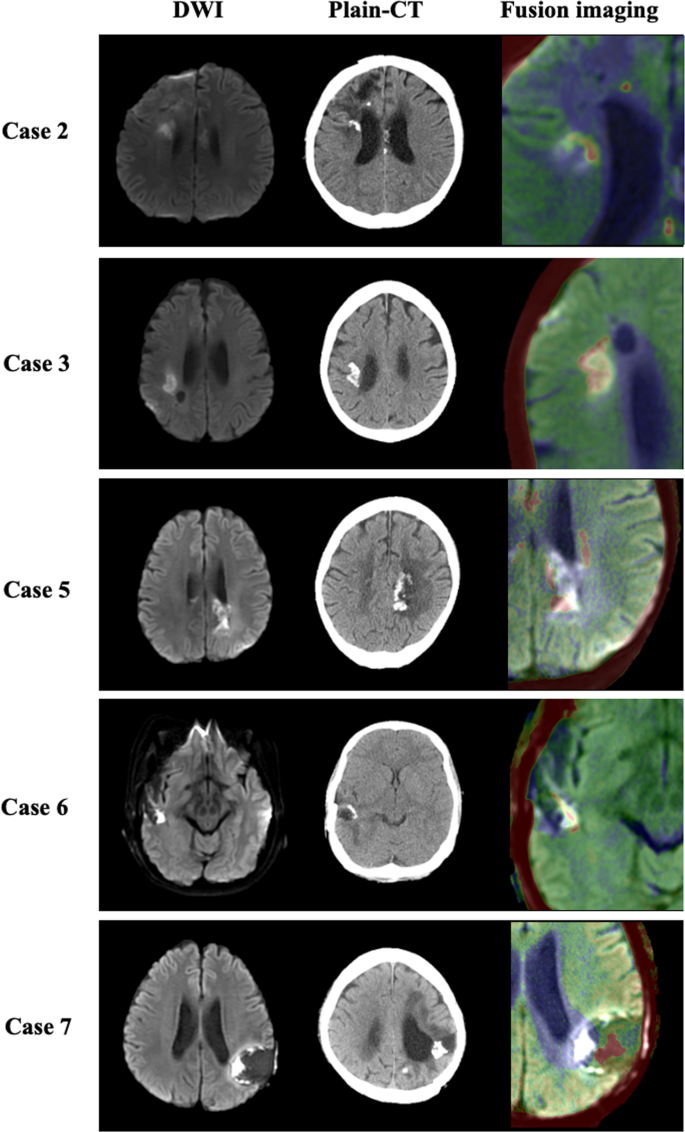

In 12 (70.6%) of 17 patients with calcification (Table 2), diffusion-restricted lesions coincided spatially with calcifications observed around the resection cavity or periventricular white matter (Fig. 3). These areas were always observed prior to the appearance of calcification, at a median of approximately 4.5 months after the initiation of BVZ treatment (Table 2). In all 12 patients, the size of diffusion-restricted lesions remained stable during a median duration of 5.5 (IQR, 2.3–19.0) months. On ASL imaging, diffusion-restricted lesions in all patients had hypoperfusion (Fig. 4a). Conversely, once diffusion-restricted lesions appeared in the non-calcification group, they gradually increased in size on DWI and had hyperperfusion on ASL imaging in all patients. These areas were ultimately diagnosed as recurrent lesions (Fig. 4b). We compared the ADC values of the two groups when diffusion-restricted lesions first appeared. The diffusion-restricted lesions in the calcification group had significantly lower ADC values than those in the non-calcification group (median, 0.56 × 10−3 mm2/s; IQR, 0.46–0.59 vs. median, 0.90 × 10−3 mm2/s; IQR, 0.84–0.99; p = 0.0031) based on the Mann–Whitney U test (Fig. 5).

Diffusion-restricted areas on diffusion-weighted imaging (DWI) (first column) and calcification lesions on plain CT (second column) were merged to create fusion images (third column) using SYNAPSE VINCENT software in five cases with calcification (Cases 2, 3, 5–7 in Table 2). Calcifications appear as red areas and diffusion-restricted lesions appear as white areas on the merged images.

In most patients with calcification, diffusion-restricted lesions coincided with calcification on CT (Fig. 3). These lesions were always observed prior to the appearance of calcification. Furthermore, diffusion-restricted lesions in the calcification group had significantly lower ADC values than those in the non-calcification group (Fig. 5). Since diffusion-restricted lesions appeared approximately a median of 4.5 (IQR, 1–20) months earlier than calcifications (12.0 months) after the initiation of BVZ treatment (Table 2), they seem to be useful as a favorable prognostic factor in patients with HGG treated with BVZ to judge treatment response to BVZ at an earlier stage. Bähr et al. reported the appearance of T1 hyperintense lesions at a median of 55 days and subsequently identified calcification at a median of 163 days after the initiation of BVZ treatment in some patients with recurrent glioblastoma14. They argue that T1 hyperintense lesions are related to the presence of calcification because the calcified areas shortened the T1 relaxation time of protons next to the surface of the calcium crystals15. In the present study, 7 (41.2%) of 17 patients in the calcification group had T1 hyperintense lesions prior to the appearance of calcifications at a median of 9.0 months after BVZ initiation, which was lower than the proportion of patients with the appearance of diffusion-restricted lesions (12 of 17 patients, 70.6%). T1 hyperintense lesions appeared in the same areas as diffusion-restricted lesions at the same time (three patients) or later (two patients). However, the remaining two patients did not develop diffusion-restricted lesions. Hence, the sensitivity and specificity of T1 hyperintense lesions seem somewhat lower than those of diffusion-restricted lesions.